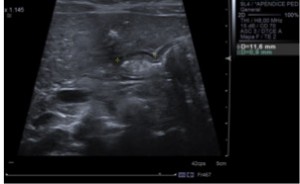

DIAGNÓSTICO FINAL: ESTENOSIS HIPERTRÓFICA DE PÍLORO

Diagnóstico ecográfico: canal pilórico > 16 mm de longitud y capa muscular > 3 mm de espesor.